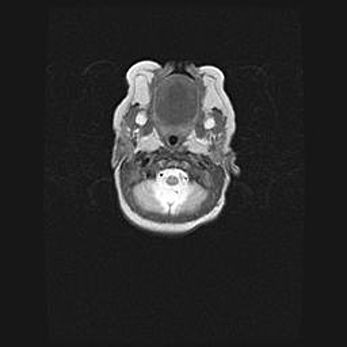

Подострая гематома правой гемисферы мозжечка.

Наружная гидроцефалия.

Возраст: 15 дней

Вес: 3100 г

Пол: женский

Окружность головы: 37 см

Срок гестации: 35-36 недель

При открытой наружной форме гидроцефалии у новорожденных расширяются и переполняются субарахноидные пространства.

Кровоизлияния в мозжечок имеют две клинико-анатомические формы: полушарные гематомы и кровоизлияния в червь.

К появлению этой патологии может привести: повреждения головного мозга, возникающие в результате асфиксии и гипоксии плода при беременности, или травмы во время родов. Редко гематома мозжечка может быть результатом первичной коагулопатии и сосудистой мальформации, диссеминированном внутрисосудистом свертывании, изоиммунной тромбоцитопении.